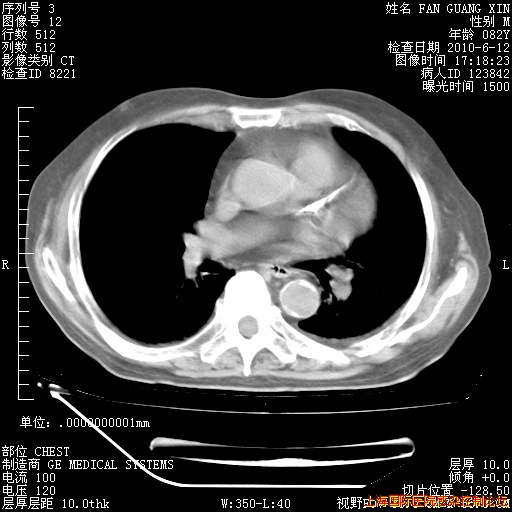

补发6月12日肺部CT肺窗

6月12日肺窗